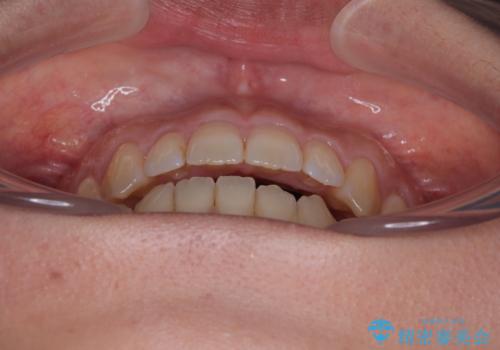

【モニター】食事が取りづらい 極端な開咬をインビザラインで解決

- 極端な開咬を気にして来院された患者様です。

開咬の方の特徴として、幼少期の指しゃぶりの癖や、強い舌の突出癖が挙げられます。

こちらの患者様も強い舌の突出癖が認められたため、矯正治療を行うにあたり、舌のトレーニングをしっかりと行っていただくように指示をいたしました。

開咬はインビザラインが得意とする歯列不正であるため、舌のトレーニングを行いながら、インビザラインにて矯正治療を行うこととしました。

担当医としては、もっと上下の前歯を接触させるところまで治療を進めたいという思いがありますが、今まで咀嚼できなかったものが食べられるようになったということで、この状態で治療終了となりました。